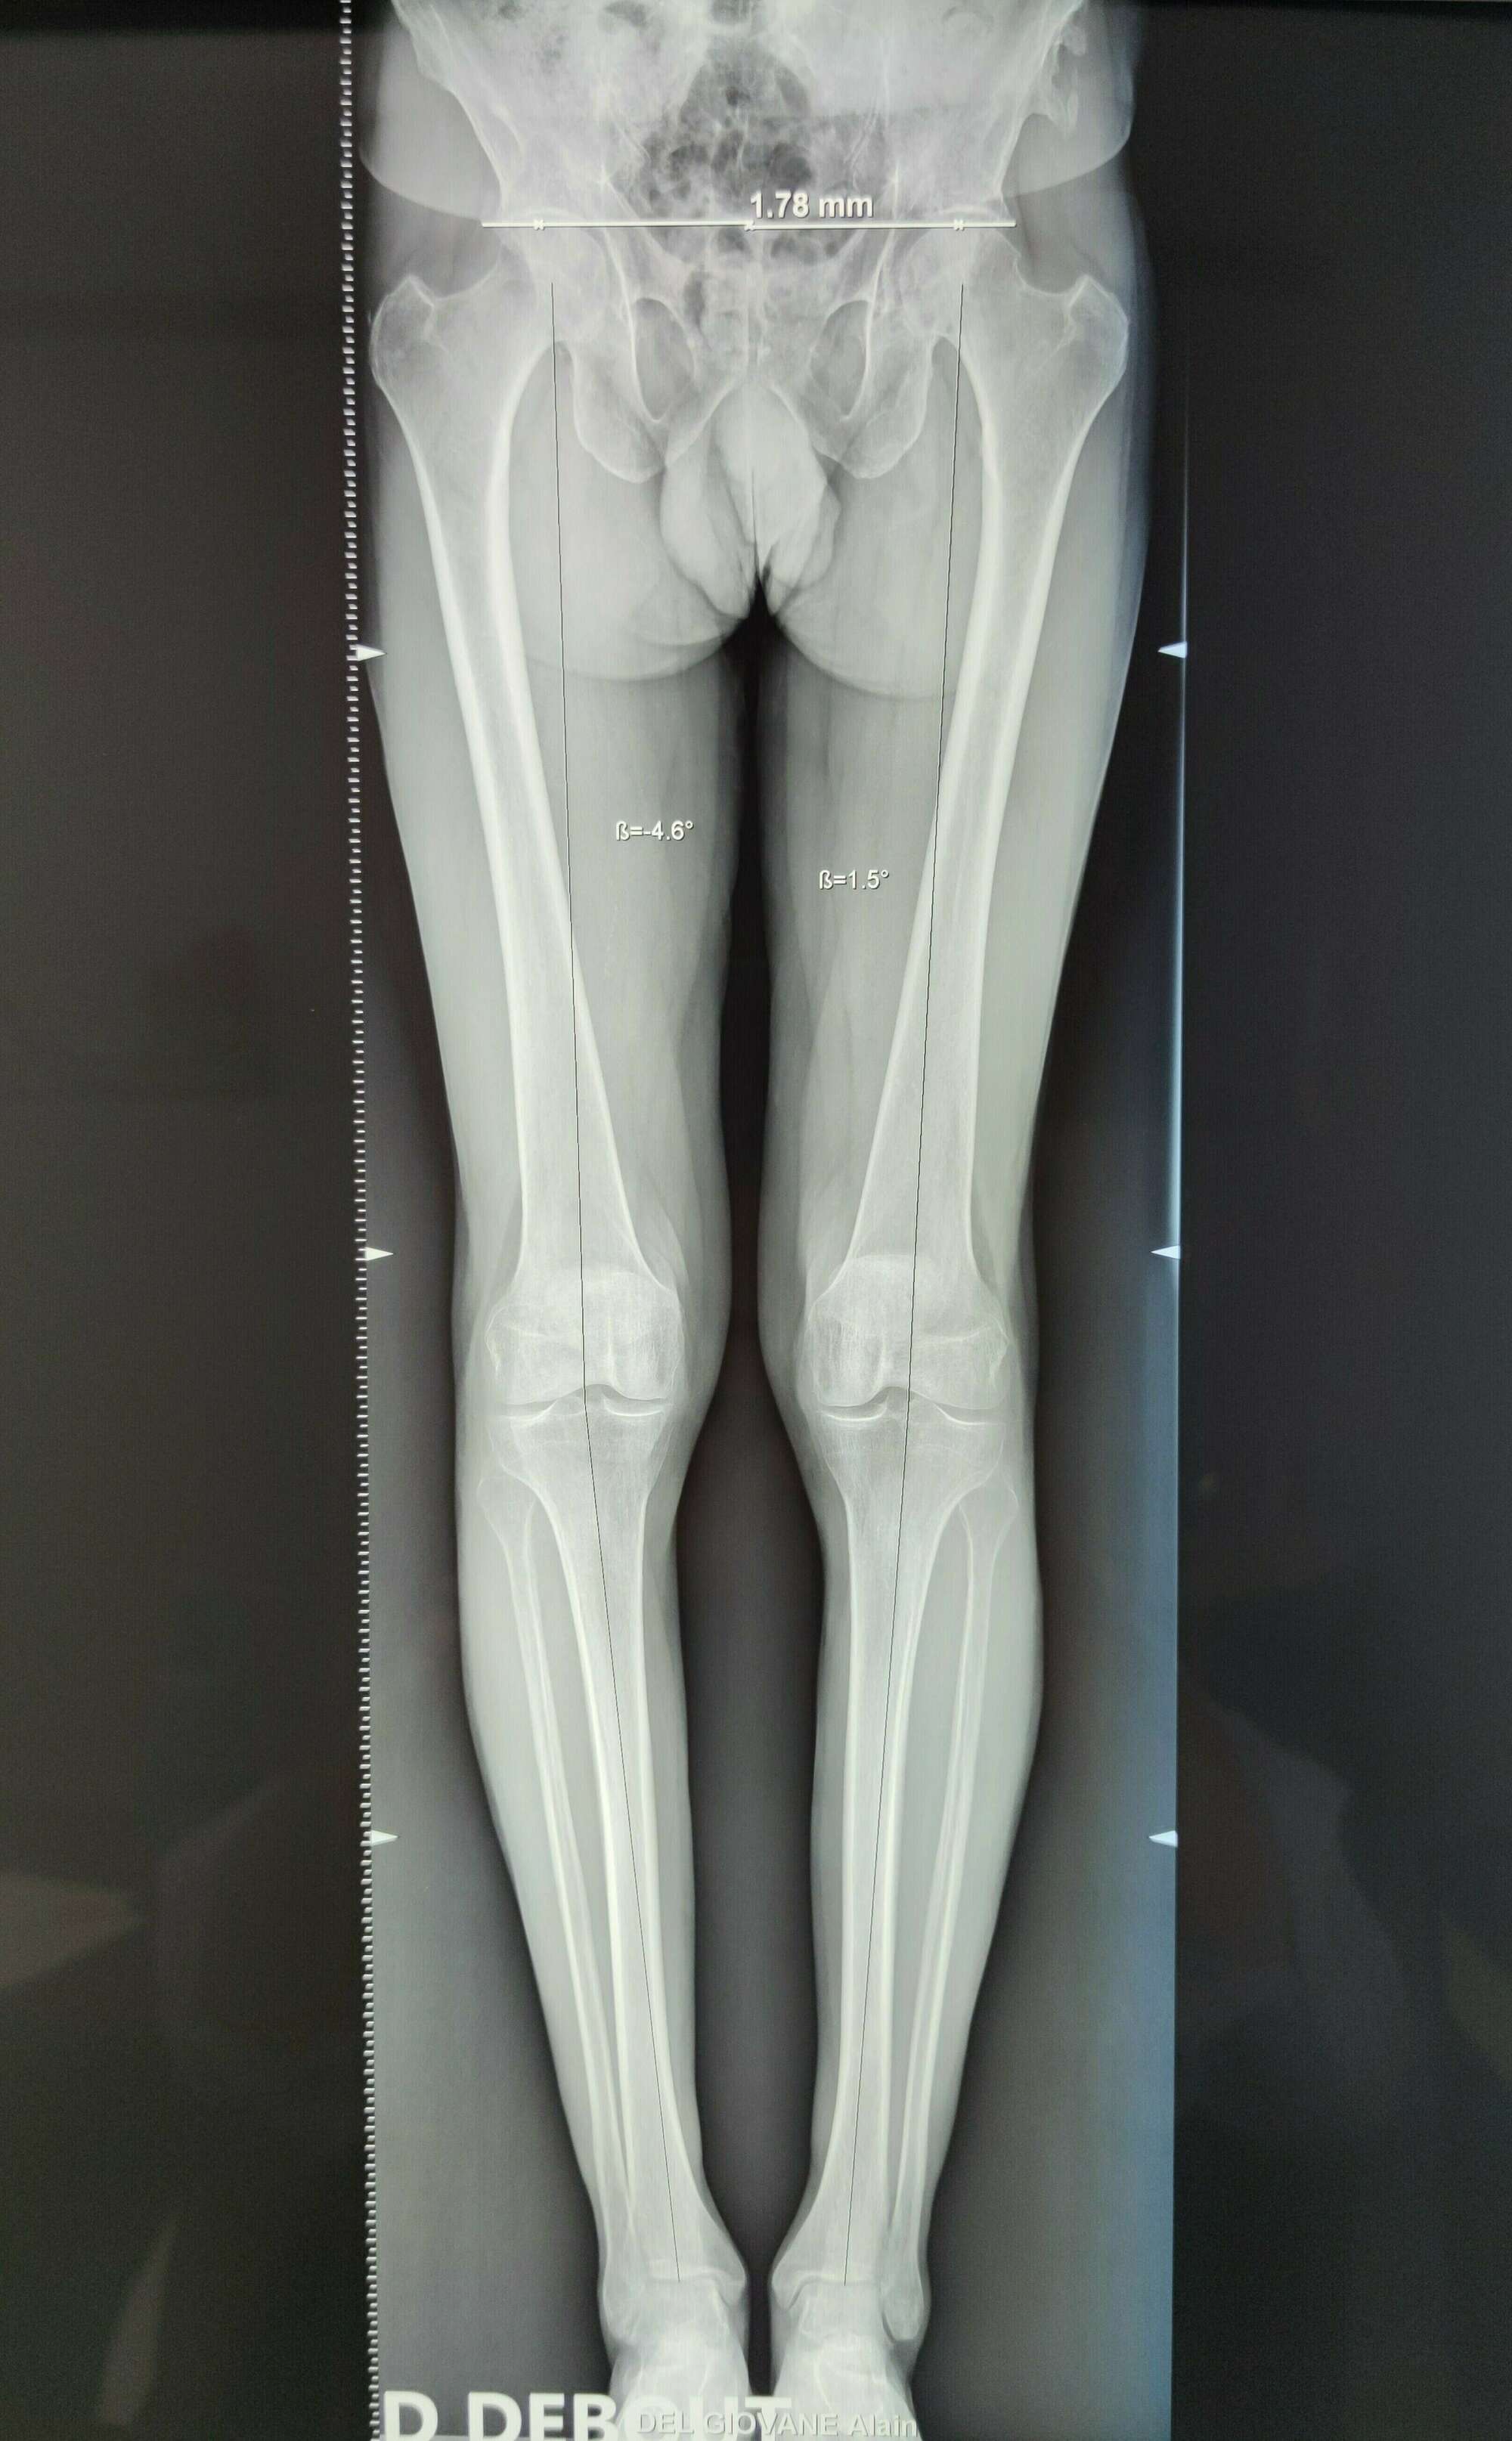

Un alternative existe pour l’arthrose mono-compartimentale : l’ostéotomie tibiale plus ou moins fémorale du genou. Elle est indiquée chez des patients présentant une arthrose légère à modérée, avec une déformation d’axe mécanique (Genu Varum plus fréquent ou Genu Valgum) et trouve sa place chez des patients jeunes, sportifs, qui pratiquent des sports à impacts non recommandés chez les patients porteurs d’une prothèse unicompartimentale. Elle reste controversée dans l’arthrose mono-compartimentale sur genou normo-axé.

- Les déformations d’axe : genu varum (jambes arquées) et genu valgum (jambe en X)